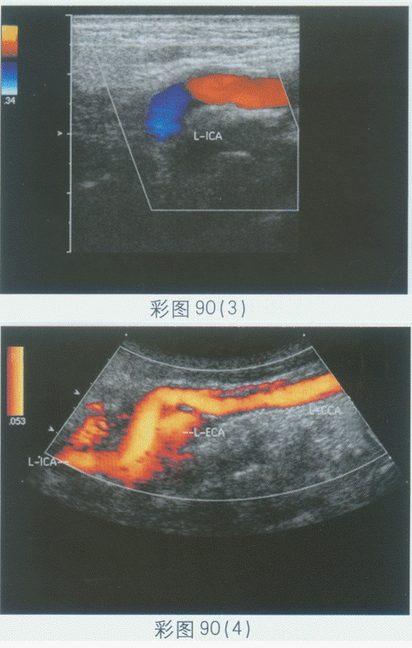

临床资料:女,74岁,自诉头晕3年加重2月余.超声综合描述:双侧颈内动脉走行纡曲,呈"S"形,CDFI:血流通畅。见彩图90。

超声提示()。

A.右侧颈内动脉走行纡曲

B.双侧颈内动脉走行纡曲

C.左侧颈内动脉走行纡曲

D.双侧颈内动脉正常声像图